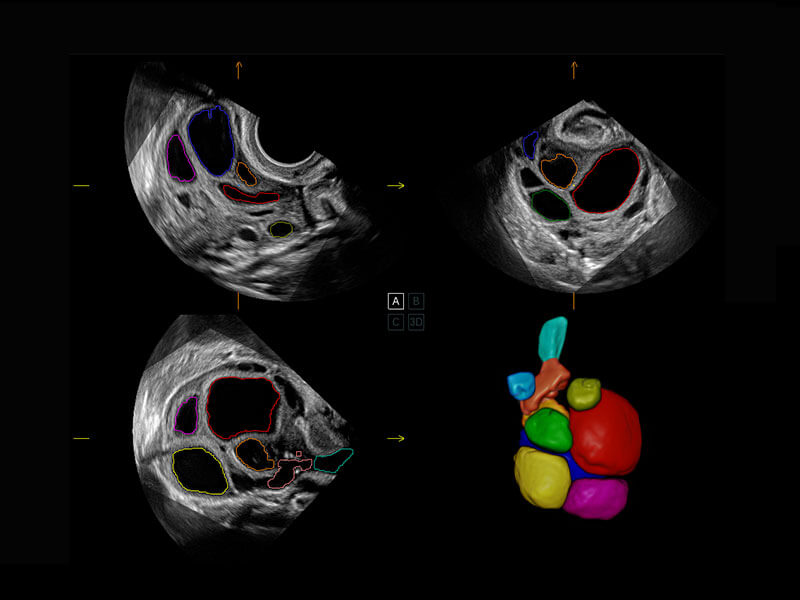

P60搭载一系列胎儿心脏成像技术,实现精细的胎儿心脏评估。

• 四腔切面

• 四腔心血流

• 右室双出口

• 胎心容积成像